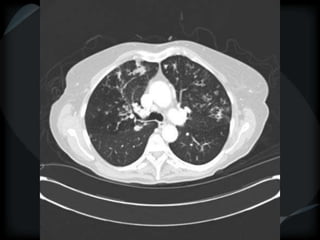

HRCT

RETICULAR PATTERN - UIP

 peripheral reticular lines / inter and intralobular septae

 honeycomb

 Traction bronchiectasis

 None or minimal ground glass

 Gradient increasing from apex to base

 Skip areas

 Diagnostic accuracy high

 Idiopathic

 Familial

 CVD - RA

 Drugs – NFT, Busulphan

 Asbestosis = basilar – bands – pleural calcification

 Chronic HP = upper and midzones

 Hermansky-Pudlak syndrome

Acute exacerbation of UIP

● above + ground glass

● Peripheral – better prognosis – Fibroblastic Foci+++

● Diffuse – worse prognosis – DAD